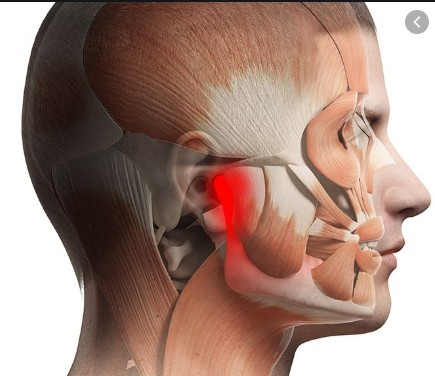

Temporomandibular joint disorders develop due to problems with the alignment between the upper and lower teeth. Temporomandibular Disorders (TMD) affect the jaw joint (TMJ) and the muscles in the face that control chewing and jaw movement. TMD can occur when the jaw opens, closes, or moves from side to side. Pain may be felt in the jaw joint itself, as well as in the surrounding facial muscles that facilitate movement.

Common symptoms include:

- Jaw pain or tenderness

- Clicking, popping, or grating sounds in the jaw Read More...

- Difficulty opening or closing the mouth

- Headaches radiating to the neck and shoulders

Treatment options include:

- Corrective bite splints

- Full-mouth rehabilitation

- Joint lavage (flushing the joint)

- Surgical intervention in severe cases